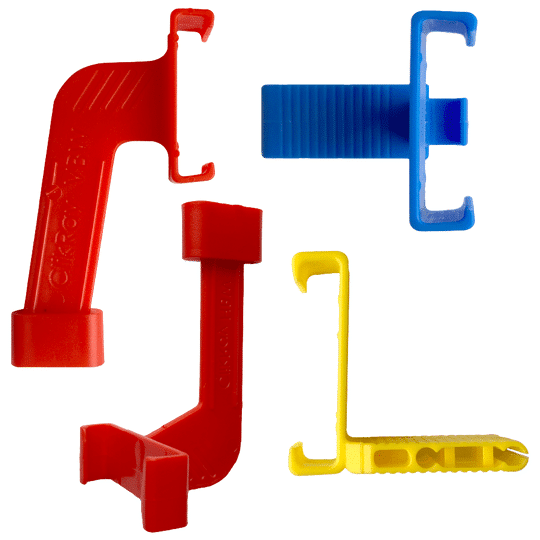

The Pro sensor combines ultra-low noise technology for crisp images with lower radiation, true-clipped corners for easier positioning, a 45° cord exit for vertical shots, and direct software integration, all designed for comfort, durability, and reliability. Plus, it's proudly made in the USA.

All of our sensors are a great fit for any office. The DentiMax Pro Sensor is our premier sensor and offers a full range of sizes and comfort. This sensor allows you to take images on small children all the way up to adults. It is designed with patient comfort in mind and also created to give offices the ease, quality, and reliability they deserve.